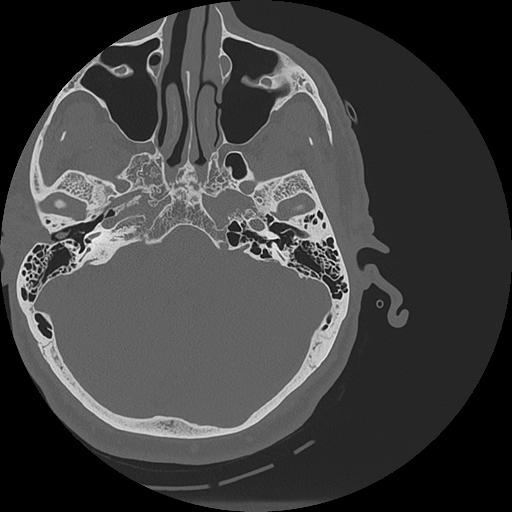

7 HUESO,,Vol,0.5,HUESO,,